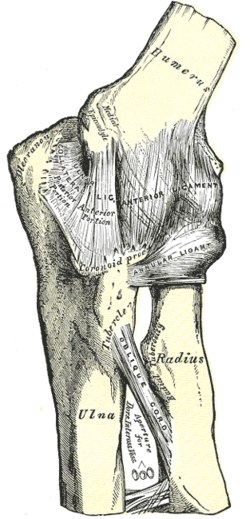

Left: anterior and ulnar collateral ligaments

Right: posterior and radial collateral ligaments

The elbow, like other joints, has ligaments on either side. These are triangular bands which blend with the joint capsule. They are positioned so that they always lie across the transverse joint axis and are, therefore, always relatively tense and impose strict limitations on abduction, adduction, and axial rotation at the elbow.[7]

The ulnar collateral ligament has its apex on the medial epicondyle. Its anterior band stretches from the anterior side of the medial epicondyle to the medial edge of the coronoid process, while the posterior band stretches from posterior side of the medial epicondyle to the medial side of the olecranon. These two bands are separated by a thinner intermediate part and their distal attachments are united by a transverse band below which the synovial membrane protrudes during joint movements. The anterior band is closely associated with the tendon of the superficial flexor muscles of the forearm, even being the origin of flexor digitorum superficialis. The ulnar nerve crosses the intermediate part as it enters the forearm.[7]

The radial collateral ligament is attached to the lateral epicondyle below the common extensor tendon. Less distinct than the ulnar collateral ligament, this ligament blends with the annular ligament of the radius and its margins are attached near the radial notch of the ulna.[7]